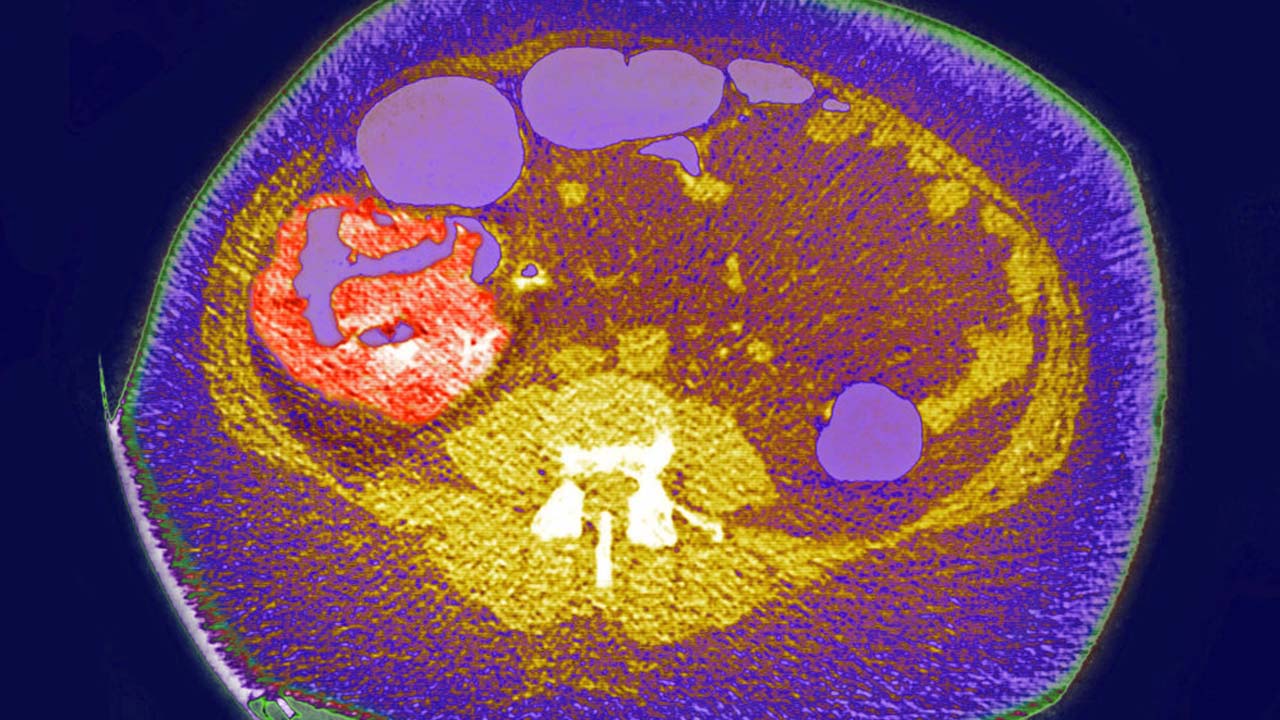

Doctors are warning patients that colon cancer is on the rise in people under 55.

The National Cancer Institute says colon cancer is now the leading cause of death for adults aged 20-49 and with the death of 48-year-old James Van Der Beek this week, colon cancer is getting a lot of attention.